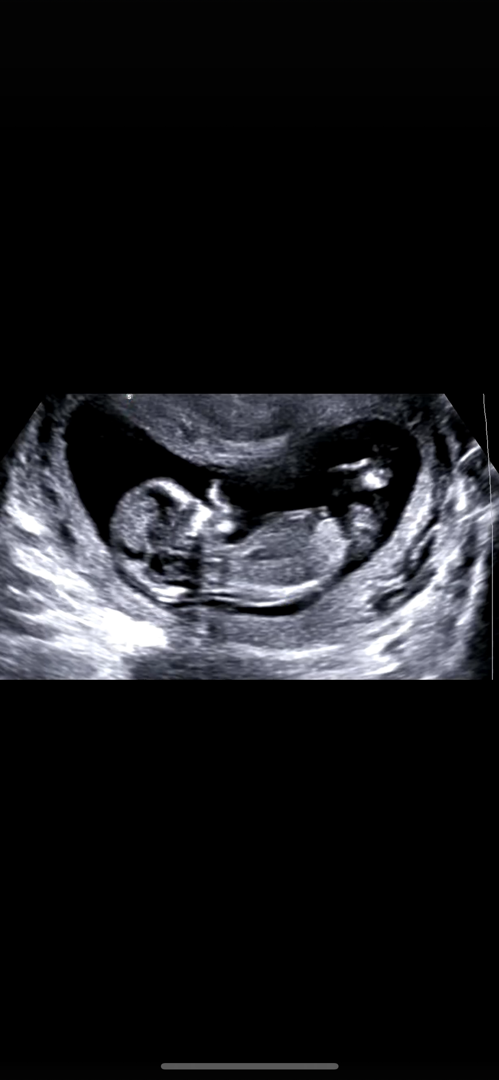

12주 각도법 봐주세여

각도법 부탁드려요 ㅠ